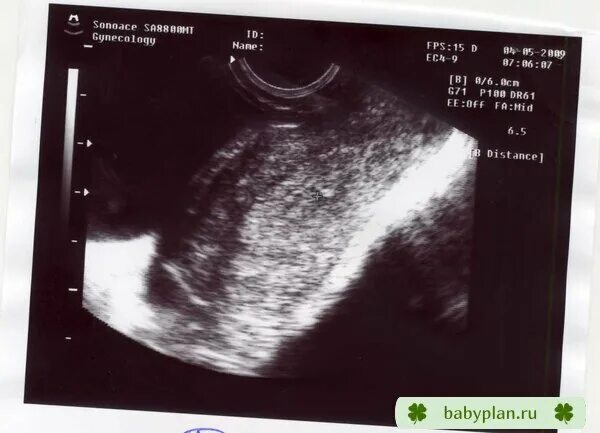

Задержка 2 недели какой срок